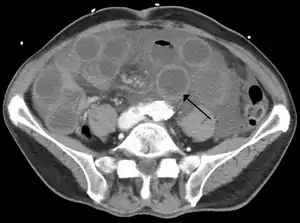

Computed tomography (CT) showing dilated loops of small bowel with thickened walls (black arrow), findings characteristic of ischemic bowel due to thrombosis of the superior mesenteric vein.

Risk factors for acute mesenteric ischemia include atrial fibrillation, heart failure, chronic kidney failure, being prone to forming blood clots, and previous myocardial infarction.[2] There are four mechanisms by which poor blood flow occurs: a blood clot from elsewhere getting lodged in an artery, a new blood clot forming in an artery, a blood clot forming in the superior mesenteric vein, and insufficient blood flow due to low blood pressure or spasms of arteries.[3][6] Chronic disease is a risk factor for acute disease.[7] The best method of diagnosis is angiography, with computed tomography (CT) being used when that is not available.[1]